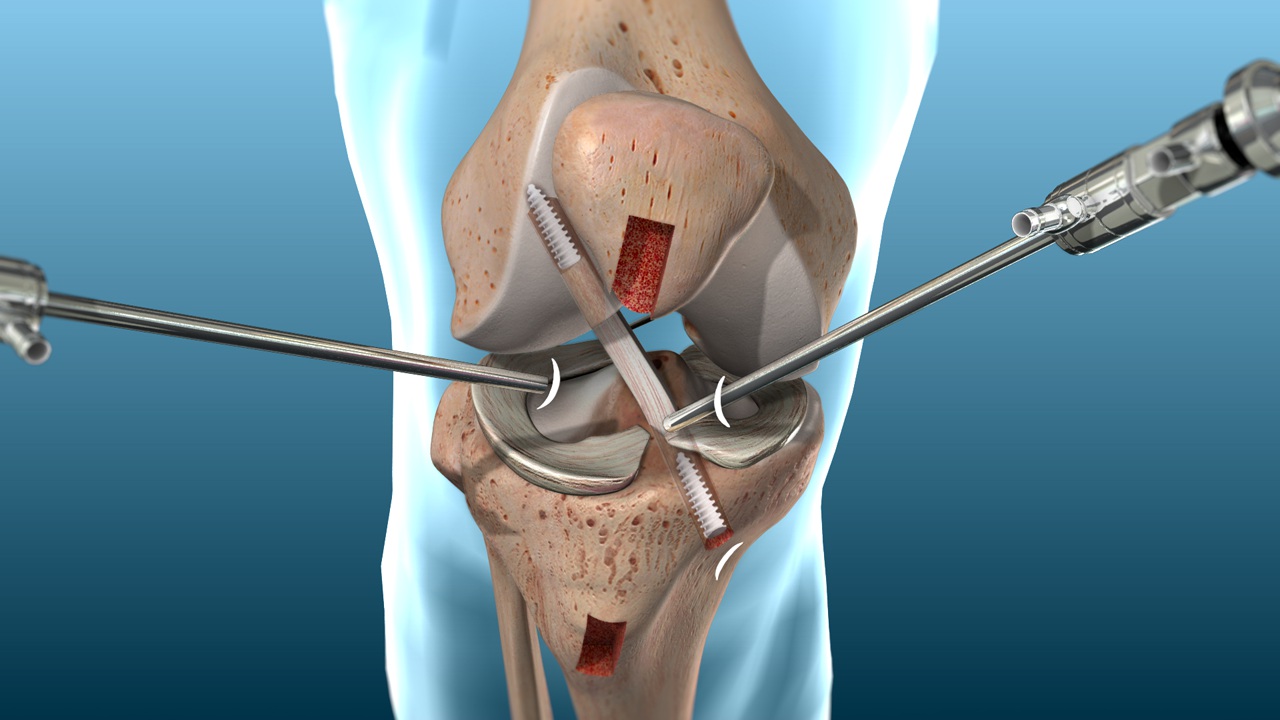

La reconstruction du LCA consiste à remplacer le ligament endommagé par un greffon, qui peut provenir des propres tissus du patient ou d’un donneur, selon les facteurs individuels. L’intervention est généralement réalisée par arthroscopie, ce qui permet une reconstruction précise avec un minimum d’atteinte aux tissus environnants.

L’approche chirurgicale est choisie en fonction de l’anatomie du genou, des lésions associées et des objectifs spécifiques du patient.